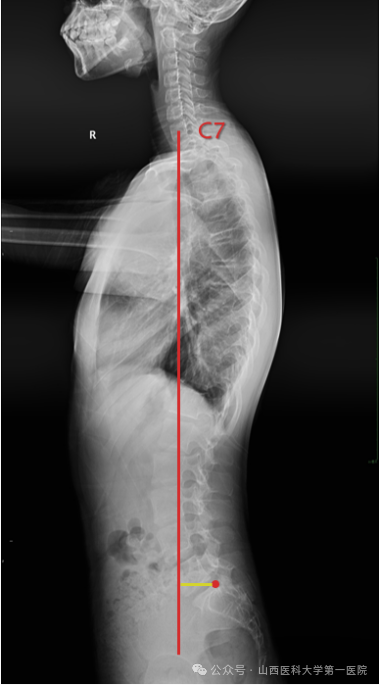

4. C7垂线(C7PL)

C7垂线是C7椎体中心垂直向下的直线,与X线片垂直边缘平行。通过测量C7垂直线与S1(CSVL)中心垂线之间的横向距离,可以确定冠状面的平衡。C7PL-CSVL代表C7PL和CSVL的水平间距。C7PL位于CSVL右侧为正值,左侧为负值,C7PL-CSVL>2cm定义为冠状面失衡。

7. 矢状面垂直轴(SVA/SVAO)

矢状面垂直轴定义为从C7垂直线到S1后角的偏移量。SVA的正常范围尚未确定,可能介于前2.5cm后5.0cm之间。矢状面垂直轴(SVA/SVAO)常用于判断脊柱矢状位有无失衡的一个重要指标。